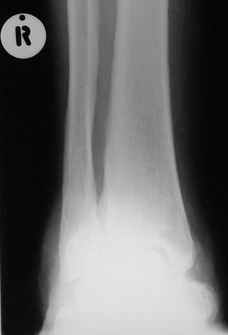

После меня выступал с новыми находками для своей коллекции Эмануэл Лакью Тесема, хирург-ортопед из Эфиопии: Мне понравились его находки:

Кто шустрый - при какой патологии встречается так называемые "суставы Шарко"?Второе приобретение доктора Эмануэла мне понравилось своим романтическим названием: Candle bone - <кость-в-виде-оплывающей-свечи> : Просто редкая патология:

VR>Второе приобретение доктора Эмануэла мне понравилось своим романтическим названием: Candle bone - <кость-в-виде-оплывающей-свечи> : Просто редкая патология:

Мелореостоз

Под названием "мелореостоз" описано около 50 случаев врожденного заболевания скелета, выражающегося в совершенно

своеобразном одностороннем остеосклерозе костей одной только конечности. Можно не сомневаться в том, что

мелореостоз встречается далеко не редко; мы наблюдали свыше 20 случаев. Вполне естественно, что отдельные новые

казуистические наблюдения, не вносящие в науку никаких новых фактов и не возбуждающие новых мыслей и обобщений,

остаются неопубликованными.

Остеосклероз при этом заболевании захватывает не всю кость по окружности, а простирается слегка волнистой

полосой вдоль длинной оси конечности (рис. 223, К), переходя через линию суставов на другие кости. Таким образом,

может оказаться пораженной целая верхняя или нижняя конечность или больший или меньший ее периферический участок,

например, часть лопатки, полуцилиндр плечевой кости, часть цилиндра лучевой кости и скелет II пальца вместе с

лежащими по этой оси участками запястных костей или же часть - медиальная или латеральная - бедренной,

болынеберцовой кости с продолжением и расширением процесса на предплюсневые и плюсневые кости и соответствующие

по длиннику фаланги одного или нескольких, но никогда не всех пальцев. Описавшие эту болезнь в 1922 г. Жоани

(Joanny) и Лери (Leri) сравнивают остеосклеротические полосы с картиной, напоминающей стекающий со свечи и

застывающий стеарин или воск, отсюда и название "мелореостоз" - "стекающая вдоль конечности кость".